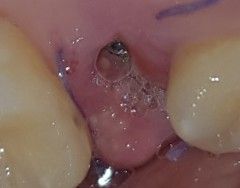

근데 뼛가루가 막...엄청 많더라구요 ㅠㅠ 이게 원래 이럴 수 있는건가요? 명절이라 치과가 영업을 안해서 여기에 여쭙습니다 ㅠㅠ

• 2번 째 사진

해당 사진으로 보아서는 크게 문제가 되지 않을 것으로 보입니다. 임플란트 술식을 할 때 뼈이식을 같이 한 것으로 보이며 상부에 남아 있는 뼈가 노출되었거나 기존의 뼈와 융합되지 못하고 탈락한 뼈이식재가 나온 것으로 보입니다. 잇몸 자체에 발적이나 부종 등이 없으므로 큰 문제는 없을 것으로 보이나 x-ray를 한 번 촬영하는 것은 도움이 될 것으로 보입니다.

뼈이식을 같이 하신거 같은데 뼈가루가 조금씩 나오는건 크게 상관없습니다. 너무 걱정은 하지 마시고 치과에 가셔서 엑스레이 사진을 찍어보시면될것같습니다.